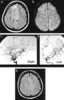

Idiopathic multiple arterial stenoses